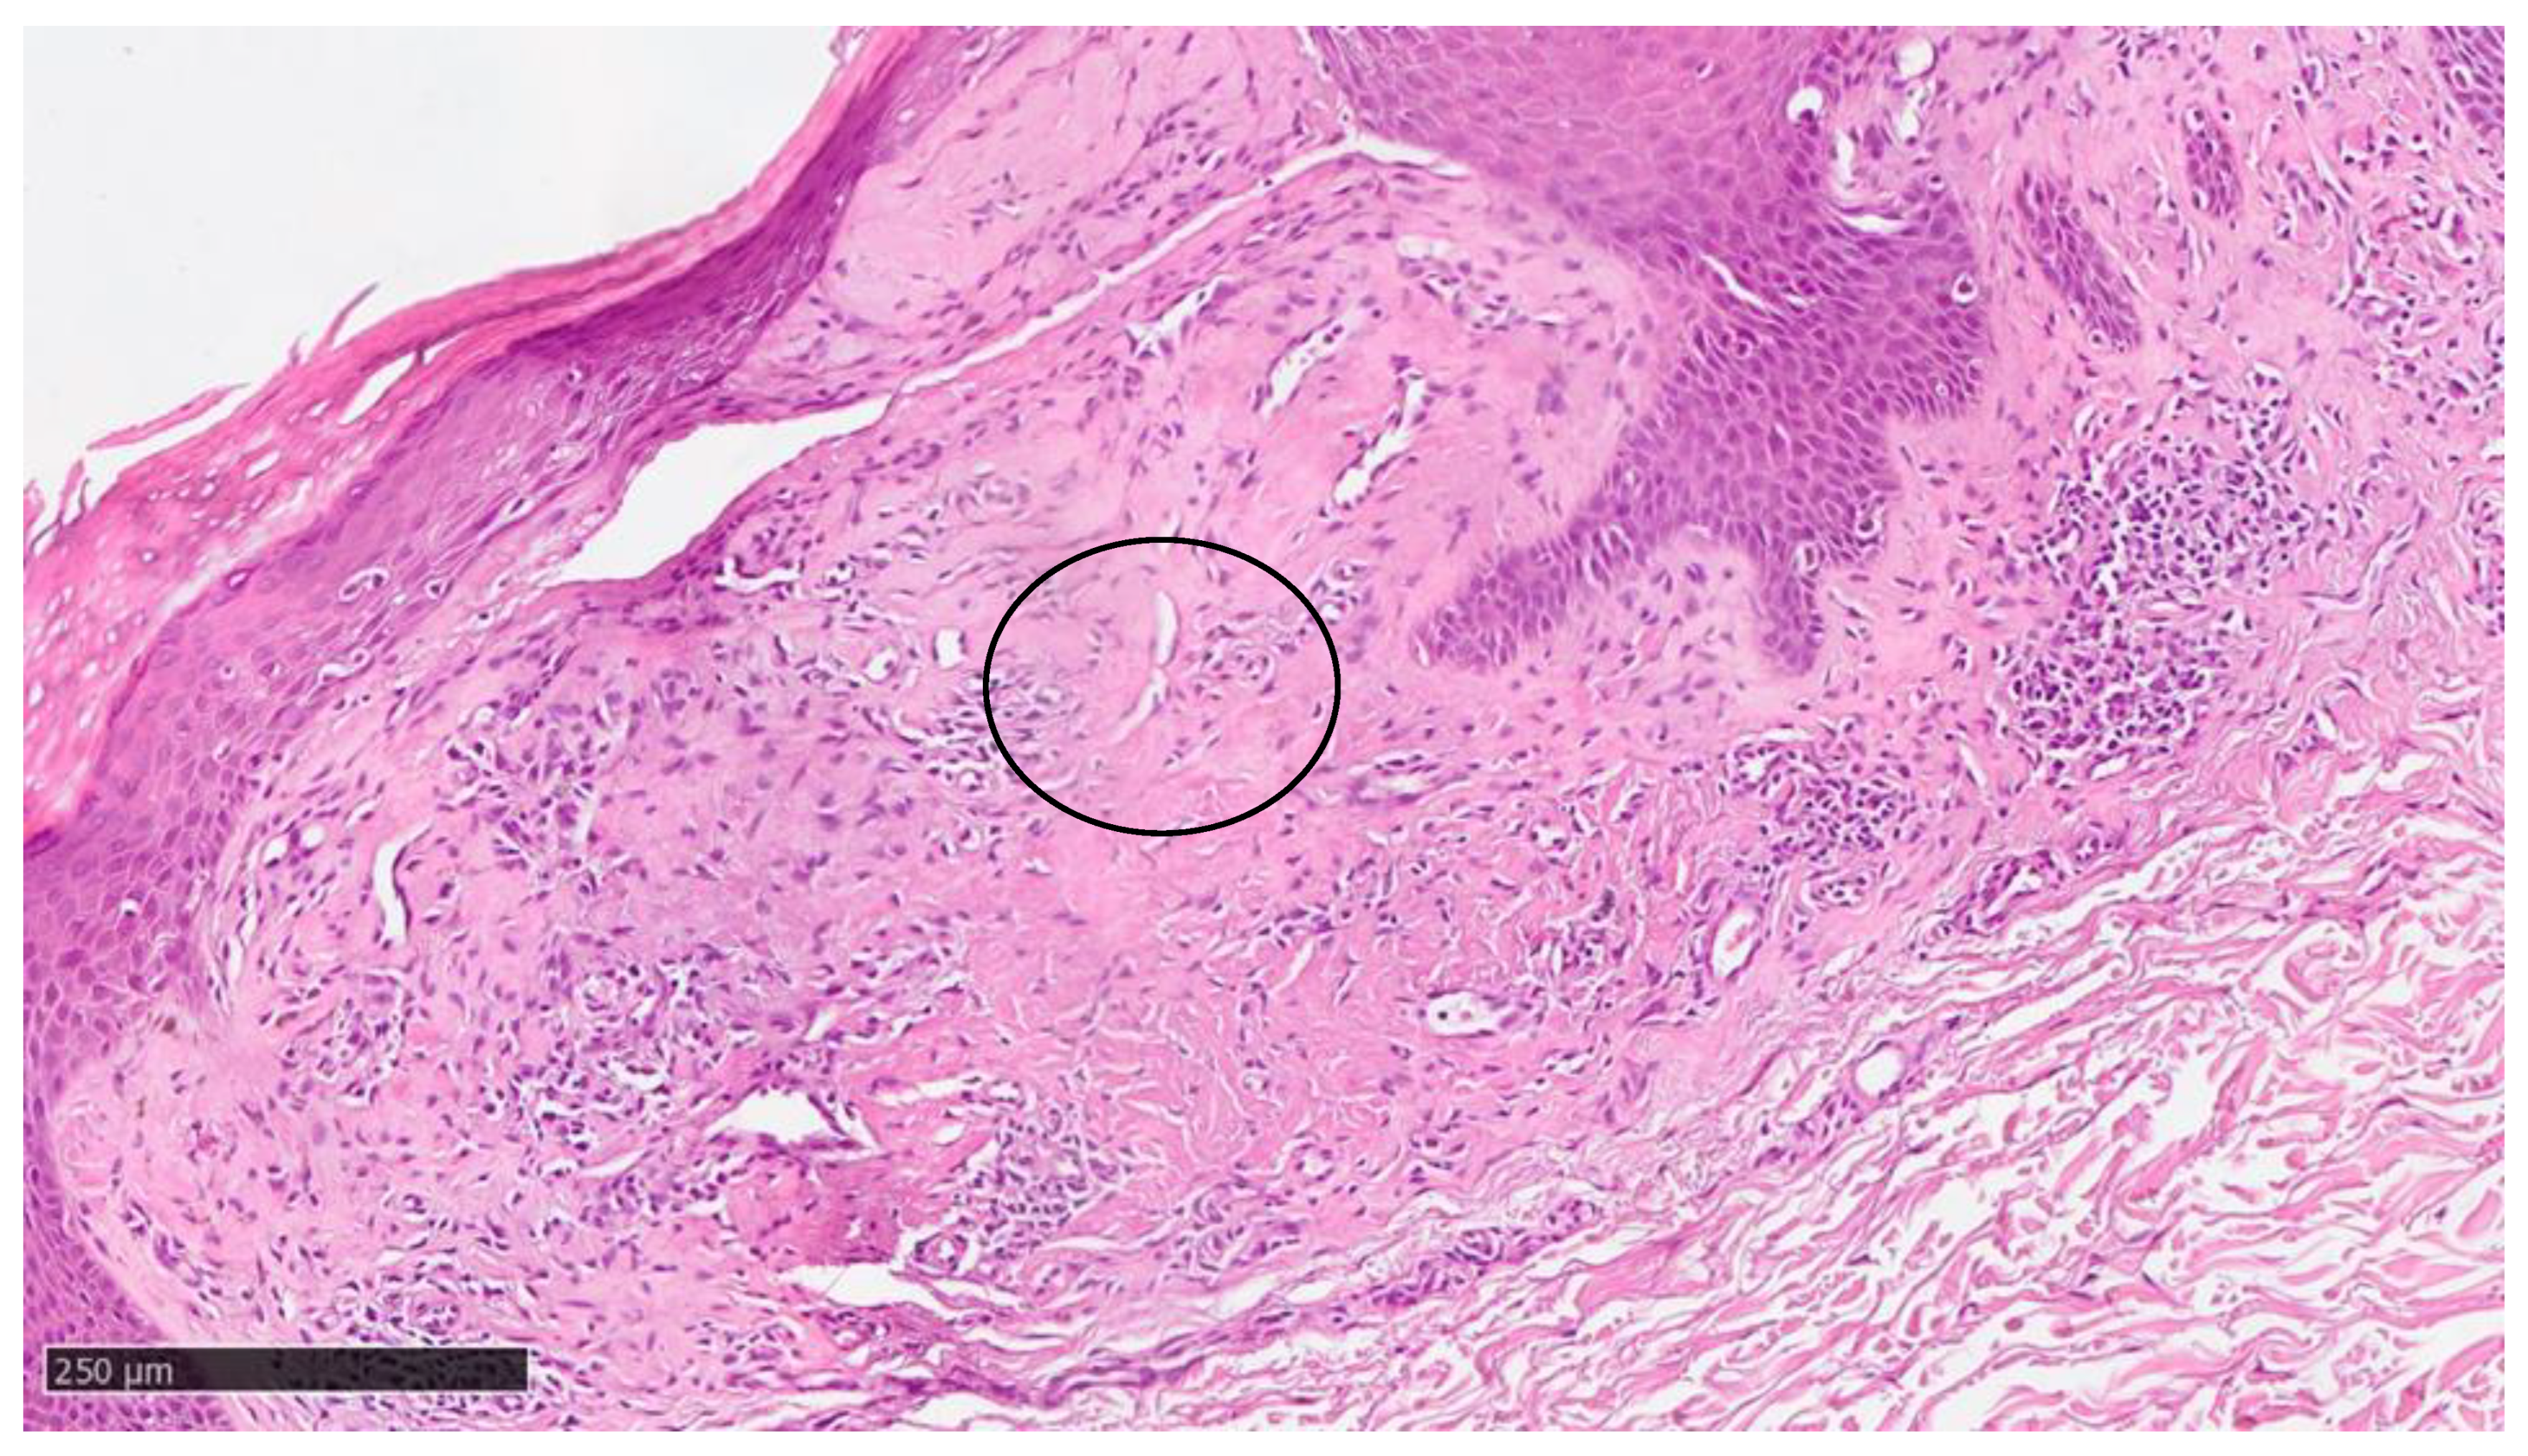

At our clinic, for a diagnosis of certainty regarding LA, an incisional biopsy was performed regarding the typical infiltrated plaques on the lower limbs. The histopathological investigations reported typical LA findings, such as the deposition of amyloid material at the papillary dermis, beneath the dermo-epidermal junction; there were also some areas with inconsistency regarding the melanic pigment and diffuse inflammatory infiltrate at the middle and superficial dermis. The epidermis was not interested in this infiltration and acts as an innocent bystander with acanthosis, hyperkeratosis, and elongation of the epidermal ridges (Figure 3, Figure 4 and Figure 5). With polarized microscopy, it was possible to appreciate the amyloid deposits beneath the dermo-epidermal junction (Figure 6).

Figure 5. Higher magnification showing some incontinence of melanin within amyloid deposition and with cleft (black circle) (hematoxylin–eosin; original magnification 20×).